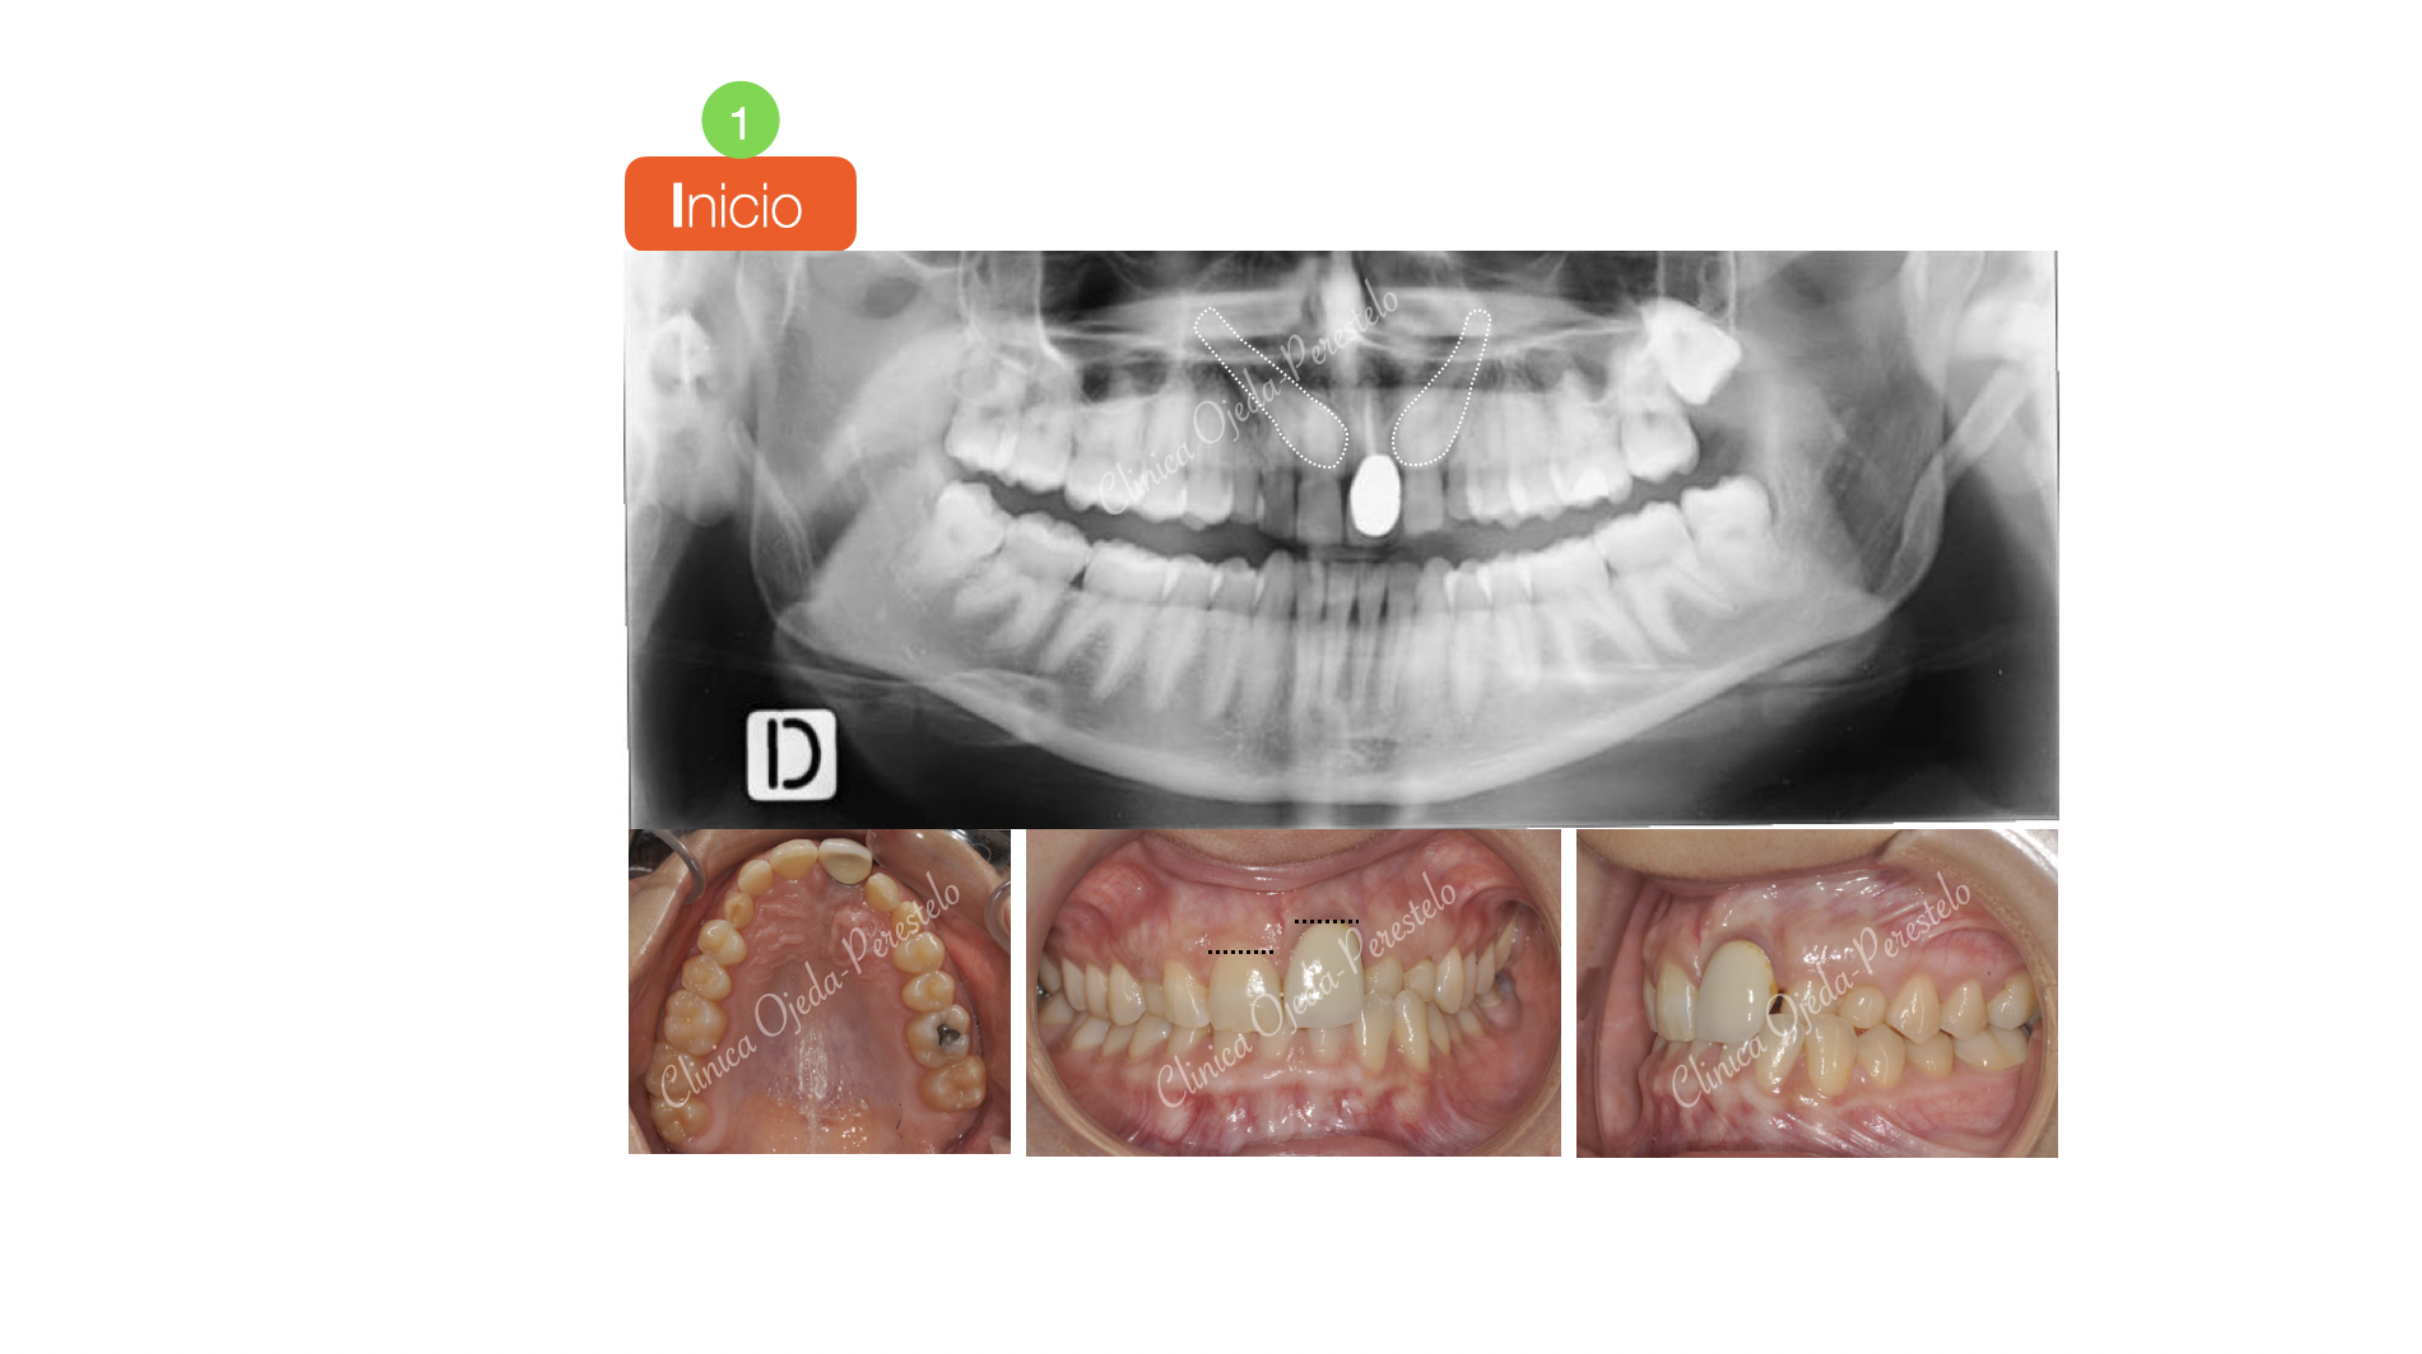

Caninos Maxilares Retenidos (13-23) + Bioestética 21-22

Presentamos a una paciente adulta con los caninos maxilares retenidos y sin posibilidad alguna de erupcionar de manera natural. Su estudio detallado nos confirma  que se encuentran por palatino y con un pronóstico de tracción incierto. Decidimos fenestrarlos e implementar una combinación de vectores distal-extrusivo y vestibular hasta su correcta reubicación dentro de la arcada utilizando como anclaje 2 MT. Este protocolo nos permite proteger de posibles reabsorciones radiculares a los dientes de apoyo.

También hemos ido extruyendo y perfilando la corona sobredimensionada de la pieza 21 hasta dotarle de una proporción adecuada.

Quisiéramos destacar la reubicación y correcta articulación de ambos caninos en la arcada maxilar así como la adecuada colocación del margen gingival de la pieza 21 en relación al 11. Una vez finalizada la Ortodoncia la  paciente se ha realizado un masking dental en la pieza 22 un cambio de corona de la pieza 21. Todo ello le ha dotado de un aspecto más natural a la sonrisa.